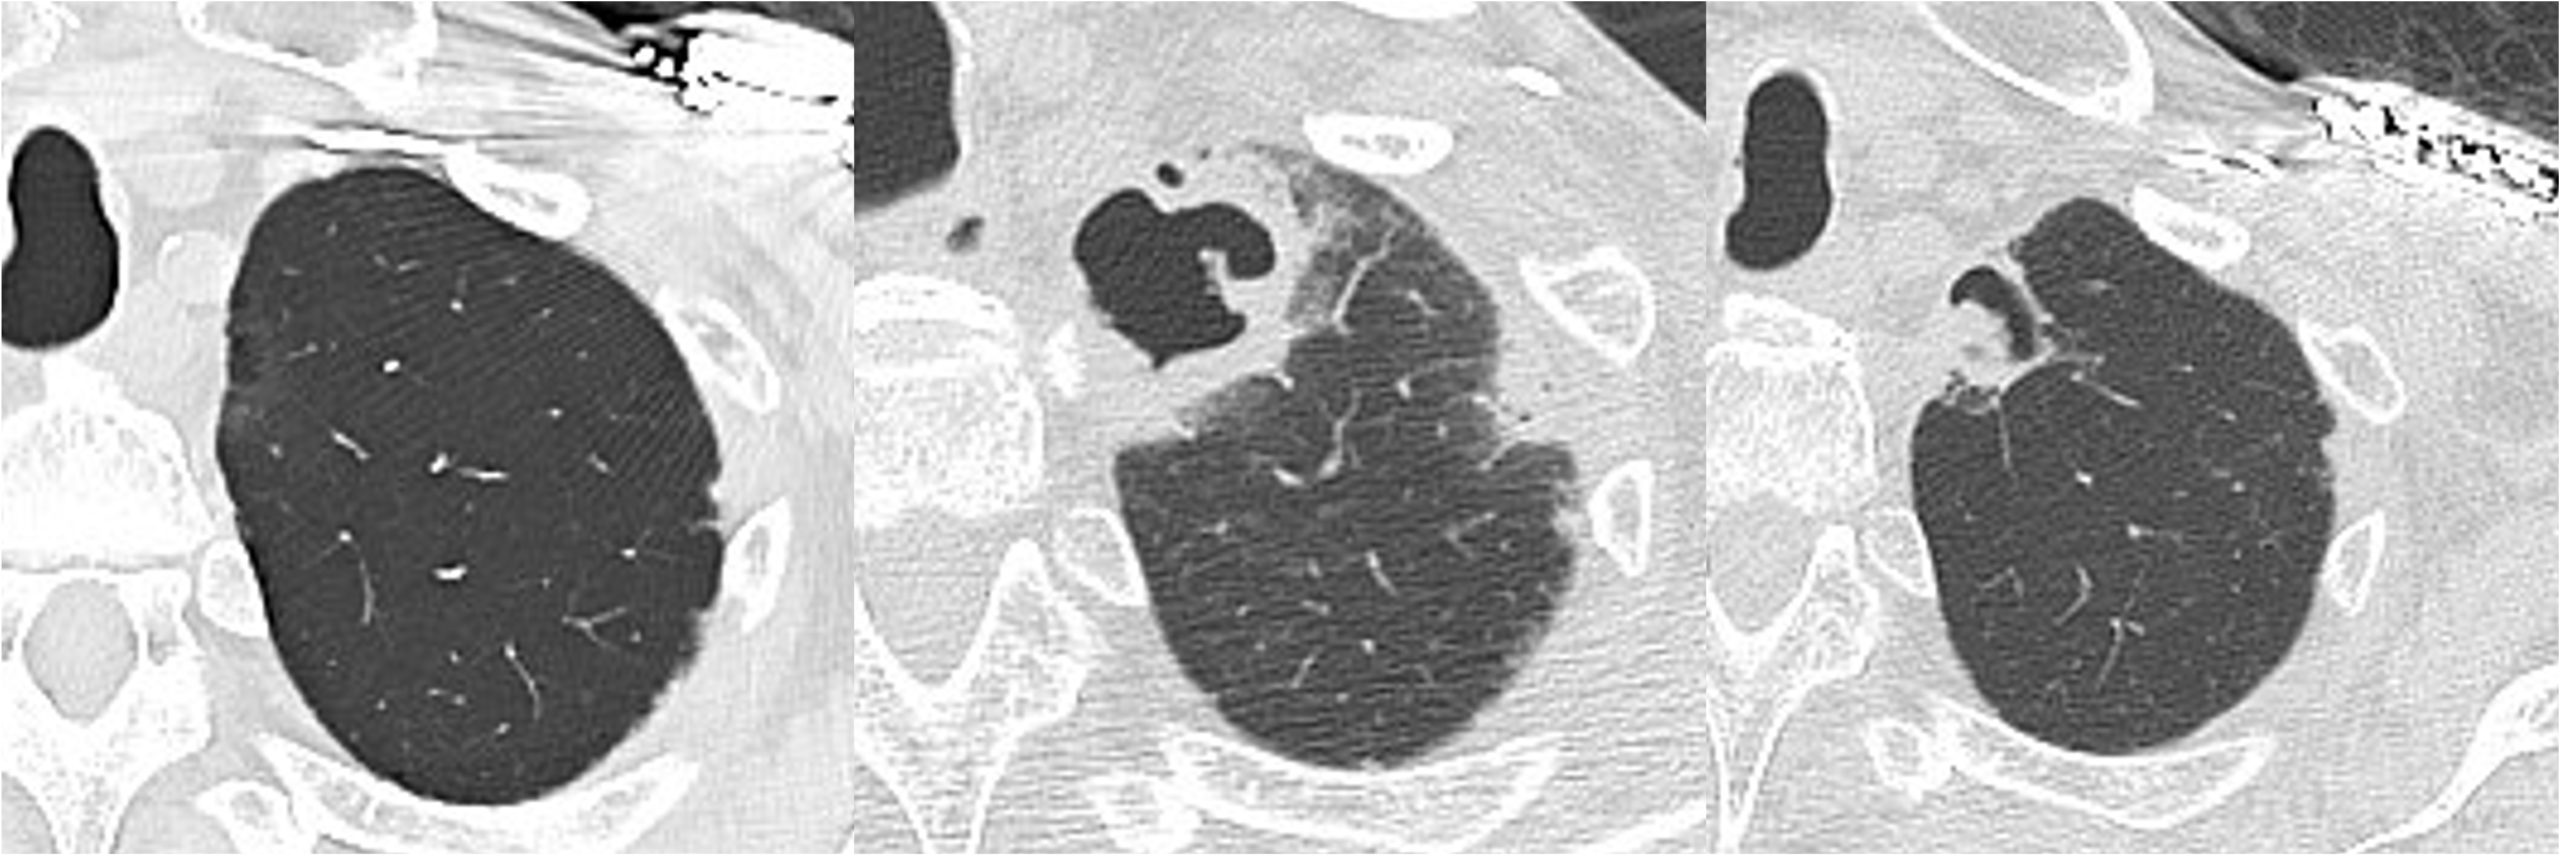

Case Presentation: A 77-year-old man presented with altered consciousness. His medical history included type 2 diabetes mellitus, hypertension, and complete atrioventricular block managed with a pacemaker. Three months earlier, corticosteroid therapy was initiated for acute lung injury of unknown etiology, with symptom improvement followed by dose tapering. He had no history of tuberculosis, mycobacterial infections, or smoking.On the day of presentation, he was found unresponsive by family members. On admission, his vital signs included a body temperature of 34.3°C, heart rate of 78 bpm, respiratory rate of 18 breaths/min, oxygen saturation of 98% on room air, and blood pressure of 117/60 mmHg. His Glasgow Coma Scale score was E4V2M5. Physical examination revealed diminished breath sounds bilaterally in the upper lung fields.Laboratory tests showed severe hypoglycemia (blood glucose 21 mg/dL), leukocytosis (16,000/μL), and elevated C-reactive protein (14.72 mg/dL). Serum Aspergillus galactomannan antigen was positive (index 0.7), and β-D-glucan was mildly elevated (10.2 pg/mL). Chest CT revealed a thin-walled cavity in the right apex and a thick-walled cavitary lesion in the left apex. Acid-fast bacillus smear tests were negative.Hypoglycemia was corrected, and the patient’s consciousness improved. Broad-spectrum antibiotics (ceftriaxone) were initiated, and bronchoscopy with bronchoalveolar lavage and biopsy confirmed the presence of Aspergillus fumigatus, leading to a diagnosis of chronic pulmonary aspergillosis (CPA). Voriconazole therapy was started after discharge. Follow-up CT at three and six months revealed reduced cavitary lesions and development of a fungal ball (aspergilloma) in the left cavity.

Discussion: This case demonstrates the rapid onset of CPA within three months of corticosteroid therapy, emphasizing its potential for accelerated progression in immunosuppressed individuals. While CPA typically evolves over months to years, this case highlights the need for early inclusion of CPA in the differential diagnosis of cavitary lung lesions, especially in patients on corticosteroids.The subacute presentation observed in this case aligns with poorer prognostic outcomes, underscoring the urgency of prompt diagnosis and initiation of antifungal therapy. Early treatment with voriconazole likely contributed to the patient’s favorable clinical and radiological outcomes.Dynamic imaging findings further distinguish this case. Initial CT revealed cavitary lesions without aspergillomas, while follow-up imaging after antifungal therapy showed the emergence of a fungal ball within the cavity. This progression illustrates the importance of longitudinal imaging in monitoring CPA’s course and response to treatment. Such observations also shed light on the interaction between host immune status and disease progression.The role of the hospitalist was critical in this case. Early recognition of CPA and coordination with pulmonologists and infectious disease specialists ensured timely diagnosis and treatment. Multidisciplinary collaboration, coupled with imaging-guided monitoring, allowed for effective management of this complex case.